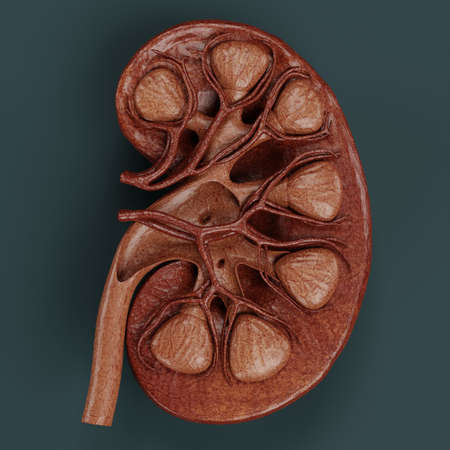

Human kidney cross section on scientific background. 3d illustration

Human kidney cross section

Human kidney cross section on science background. 3d render

Human kidney cross section. 3d illustration

Human kidney cross section.3d render

Human kidney cross section

An intricate visualization of a human kidney cross-section, highlighting the vibrant layers of the outer cortex, inner medulla, and intertwining blood vessels agains

Kidney disease. Kidney cross section. 3d illustration

Human kidney cross section on scientific background. 3d illustration

Human kidney cross section on scientific background. 3d illustration

Human kidney cross section on scientific background. 3d illustration

Human kidney cross section on scientific background. 3d illustration